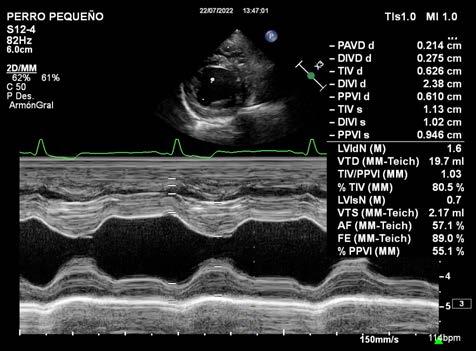

5Servicio de Anestesiología. Hospital AniCura Valencia Sur. Av. de Picassent 28. 46460 Silla (Valencia).

Resumen

La anestesia del paciente con patología cardiaca es frecuente en nuestra clínica diaria. Es por ello que en este manuscrito pretendemos abordar los conceptos hemodinámicos básicos de estos pacientes, así como las consideraciones anestésicas subyacentes para que el lector pueda enfrentarse a la anestesia de las principales patologías cardiacas adquiridas.

RPalabras clave: anestesia, cardiología, gasto cardiaco, perfusión. Keywords: anaesthesia, cardiology, cardiac output, perfusion.

Clin Vet Peq Anim 2022, 42 (3): 169-179

Introducción

Durante cualquier procedimiento anestésico los ob jetivos cardiovasculares son el mantenimiento del su ministro de oxígeno y nutrientes a todos los tejidos, la recogida de los productos de desecho y, en general, el mantenimiento de la homeostasis. Pero conseguir es tos objetivos puede volverse un verdadero desafío en pacientes con enfermedad cardiovascular subyacente.

En pacientes con enfermedad cardiovascular, la opti mización del suministro de oxígeno requiere entender la fisiopatología de la enfermedad cardiaca que presen ten. Cada patología cardiaca genera unas característi cas clínicas específicas, al igual que el grado de seve ridad de la misma, la cual puede dar lugar a pacientes compensados y descompensados.1

En los pacientes cardiópatas es importante dominar el uso de fármacos anestésicos y las herramientas de monitorización disponibles, con el fin de equilibrar la fisiopatología de la enfermedad con los efectos de los fármacos anestésicos. En último término, se debe in dividualizar en cada paciente un plan anestésico que minimice el compromiso cardiovascular.

La presente revisión bibliográfica pretende abordar los conceptos hemodinámicos básicos, navegando por las diferentes fases de la anestesia (valoración preanes tésica, premedicación, inducción, mantenimiento y re

Contacto: agustin.martinez@anicura.es

cuperación) y, por último, desarrollar los puntos clave en la anestesia de las principales patologías cardiacas. La finalidad de este escrito es que el lector pueda mane jarse con comodidad en la anestesia de estos pacientes.

Conceptos hemodinámicos básicos

Para ayudar al lector a comprender la repercusión de la anestesia en ciertas patologías cardiacas, es im portante incidir en algunos conceptos básicos sobre la fisiología y hemodinámica cardiovascular.

El gasto cardiaco (GC), que por lo general se expresa en mililitros por minuto (ml/min), se define como el volumen de sangre eyectado por el corazón (normal mente se simplifica hablando del ventrículo izquierdo) en un minuto. El GC también puede encontrarse en la bibliografía como “Volumen minuto sanguíneo”.

El GC, por lo tanto, puede determinarse de manera simplificada con la siguiente fórmula: GC= Volumen sis tólico x Frecuencia cardiaca.

El volumen sistólico (VS), medido en mililitros, pue de definirse como el volumen de sangre eyectado en cada ciclo cardiaco y es susceptible de ser estimado me diante

Debemosecocardiografía.tenerencuenta también que la presión ar terial (PA) depende directamente del GC y de la resis

169

tencia vascular periférica (RVP), siguiendo la siguiente fórmula: PA= GC x RVP.

Los pacientes que presentan una patología cardiaca verán reducido su GC, lo que se traducirá en un descen so de la PA. Este suceso hará que se pongan en marcha mecanismos compensatorios que serán beneficiosos a corto plazo, aunque más tarde se transformarán en des compensatorios y, finalmente, serán los responsables de la sintomatología de insuficiencia cardiaca.2

La caída de la PA será detectada en los barorrecep tores (principalmente aórticos y carotídeos), lo cual generará un estímulo del sistema nervioso autónomo simpático que conduce a la liberación de catecolaminas (adrenalina y noradrenalina). Esto generará vasocons tricción, aumento de la frecuencia cardiaca y aumento de la contractilidad cardiaca.

La caída de la PA también será detectada en el apa rato yuxtaglomerular del riñón, activando el sistema renina-angiotensina-aldosterona, el cual generará un aumento de la vasoconstricción, retención de sodio, cloro y, por ende, agua. De esta manera, por medio de la vasoconstricción y el aumento de la volemia, el or ganismo tiende a la elevación de la presión arterial y el retorno venoso (precarga cardiaca). El incremento de la precarga cardiaca busca un aumento de la contractili dad, mediada por la ley de Frank- Starling (Fig. 1) aun que esta solo se dará en el área dependiente de volemia, observado en la línea hasta alcanzar el punto C.

Para entender cómo los mecanismos compensatorios iniciales pueden volverse negativos para el paciente, abordaremos los siguientes puntos:

- El aumento de la frecuencia cardiaca (FC) reducirá la duración de la diástole, con lo cual disminuirá el tiempo de llenado ventricular y el tiempo de perfusión del miocardio. Además, el aumento de FC y de contractilidad también aumentará la demanda de oxígeno del miocardio, pudiendo incluso generar focos hipóxicos que podrían ocasionar arritmias.

- El aumento del tono vasomotor genera un incremento en la resistencia que debe vencer el músculo cardiaco para poder acortarse (postcarga cardiaca). Este hecho agravará un déficit de volumen sistólico.

- El aumento de la volemia repercutirá en un incremento de la precarga cardiaca de un corazón que no es capaz de bombear toda la sangre que le llega. Esto desencadenará un fenómeno congestivo e incluso edema.

La mayoría de los anestésicos tienen efectos sobre la función autónoma, el tono vascular, la FC y la con tractilidad cardiaca, por ello es imprescindible conocer las limitaciones funcionales que va a padecer nuestro

Figura 1. La curva de Frank-Starling relaciona precarga con volumen sistólico (VS) y determina dos zonas: zona de precarga-dependencia y zona de precarga-independencia. Un pequeño aumento de precarga en zona de precarga-dependencia (de A hacia B) va a provocar un gran cambio en el VS. Por el contrario, un aumento de precarga en zona de precarga-independencia (de C hacia D) resultará en leves o nulos cambios en el VS.

paciente y asegurar un protocolo anestésico en el que prevalezca un equilibrio hemodinámico, así como anti ciparnos a posibles complicaciones que puedan llegar se a dar durante la anestesia.

Otro aspecto a tener en cuenta durante la anestesia es la tendencia a la hipercoagulabilidad en algunas de estas patologías y un riesgo de tromboembolia asociada a la alteración de la hemodinamia durante la anestesia.

La patología cardiaca también repercutirá en la far macocinética de los fármacos anestésicos. Entre las principales repercusiones, podemos encontrar las si guientes:-Atendiendo a la absorción del fármaco podemos decir que la reducción del GC producirá una reducción de esta, a causa de la mala perfusión. Esto podría traducirse en inicios de acción más largos y en efectos algo más impredecibles de los fármacos anestésicos cuando se administran por vía intramuscular o subcutánea. Asimismo, las concentraciones alveolares de los anestésicos inhalatorios se verán incrementadas a causa de una reducción del gasto cardiaco, lo que produce un aumento del tiempo de tránsito de la sangre por los capilares alveolares; esto derivará en una mayor profundidad anestésica.

- En relación con la distribución de los fármacos, debemos tener en cuenta que la reducción del GC conllevará una disminución en el volumen de distribución, lo que se traducirá en un inicio de acción algo más lento. Si el paciente sufre formación de edemas, los fármacos hidrosolubles (como los bloqueantes neuromusculares) verán disminuida su respuesta. Por último, si nuestro paciente padece hipoalbuminemia (resultado de

A.170Martinez-Albiñana et al

una malabsorción por posible edema intestinal, una pérdida renal de proteínas ante una afección renal secundaria al problema cardiaco, etc.), ello daría lugar a un aumento de la fracción libre de aquellos fármacos con alta unión a proteínas (como, por ejemplo, el propofol, la lidocaína, la alfaxalona, los opioides, etc.).

- La reducción de la perfusión hepática y renal se traducirá en un retraso en el metabolismo y la excreción de los fármacos que, por ende, presentarán una duración de su acción aumentada.

Principios anestésicos en enfermedad cardiovascular Valoración preanestésica

La mayoría de las complicaciones que pueden surgir durante el procedimiento anestésico son previsibles y en gran número evitables, siendo la valoración prea nestésica una herramienta fundamental en el éxito del procedimiento anestésico-quirúrgico, ya que aporta la posibilidad de evaluar todos los aspectos críticos posi bles y estar prevenido desde el primer momento.

En la actualidad, no existe un consenso o guía que recomiende cuáles deben ser las pruebas preanestésicas ideales, pero se ha confirmado una mayor probabilidad de mortalidad perioperatoria en pequeños animales cuando los pacientes carecieron de valoración preanes tésica.3 Algunos autores sostienen que toda evidencia o sospecha de enfermedad cardiaca o respiratoria debe ser investigada antes de un procedimiento anestésicoquirúrgico por medio de radiografías, electrocardiogra ma y ecocardiografía.4 Mediante el uso de estas prue bas complementarias se garantiza el conocimiento del estado del paciente, lo que permite tomar las medidas necesarias para disminuir el riesgo del procedimiento.

Exploración física y pruebas preanestésicas

Son múltiples los estudios que evidencian las com plicaciones perioperatorias y el riesgo de morbimorta lidad en veterinaria.5-8 Previo al procedimiento, se debe realizar un examen físico completo, prestando especial atención a los sistemas cardiovascular y respiratorio. Se debe localizar y caracterizar los soplos cardiacos, los cambios en los sonidos pulmonares, el aumento de frecuencia y esfuerzo respiratorio, color de mucosa y tiempo de relleno de capilar. La presencia de pulso yugular, y las irregularidades o déficits de pul so son indicadores obvios de posible enfer medad cardiaca. El examen físico debería acompañarse de un electrocardiograma, una ecocardiografía9 o una radiología to rácica, además de la medición de la PA con el fin de diagnosticar la existencia de

cardiopatías y de definir el estado hemodinámico del paciente a intervenir.

Se debe tener en cuenta que una patología cardiaca puede producir un trastorno renal,8 por lo que debería realizarse un análisis sanguíneo completo. Una reduc ción aguda del GC puede provocar una disminución de la tasa de filtración glomerular, un aumento de la creatinina sérica y de la urea, y una disminución en la producción de orina.10,11

Estabilización previa

La anestesia debe aplazarse en todo paciente recién diagnosticado o inestable con problemas cardiacos, ex cepto que sea absolutamente necesario. Con el fin de disminuir los riesgos anestésicos, el paciente debería ser estabilizado mediante la medicación adecuada, para posteriormente evaluar de nuevo su estado y así realizar la anestesia si es posible.12

Aquellos pacientes con una insuficiencia cardiaca congestiva (ICC) izquierda con edema pulmonar de berían recibir furosemida (2 mg/kg IV cada 1-2 ho ras) hasta su estabilización. Los derrames pleurales se drenarán por completo, a ser posible. En aquellos pacientes que presenten ascitis, debe evitarse su dre naje completo, ya que puede dar lugar a un desequi librio electrolítico e hipoproteinemia. Sin embargo, si la ascitis es grave, el drenaje parcial puede mejorar la ventilación al disminuir la presión sobre el diafrag ma. La administración intravenosa de pimobendán (0,15-0,3 mg/kg) o la infusión continua de dobutami na (comenzándose a dosis bajas, 1 µg/kg/min, que se va aumentando hasta que el paciente responda) mejoran rápidamente la contractilidad miocárdica. Se recomienda en perros con insuficiencia cardiaca izquierda causada por una cardiomiopatía dilatada o enfermedad de la válvula mitral degenerativa de gra do avanzado, y que no hayan recibido previamente pimobendán, o cuando se ha dejado de administrar una dosis oral el día de la anestesia.

Pauta de medicación cardiaca previa a anestesia

Existe controversia sobre si el día de la anestesia deben administrarse los fármacos cardiacos o no. Hay que tener en cuenta que algunos de los fármacos usados para tratar la patología cardiaca tienen efecto vasodilatador, lo que puede provocar hipotensión cuando se administran junto con otros fárma cos vasodilatadores.

La fundamentalpreanestésicavaloraciónesunaherramientaparapreveniryevitarcomplicaciones

En la Tabla 1, el lector puede encontrar los medicamentos más frecuentemente administrados en el tratamiento de las patologías cardiacas, así como sus efectos secundarios más comunes y las posibles

171 2022, Vol. 42 nº3

Tabla 1. Medicamentos cardiacos habituales, así como sus efectos cardiacos más comunes y posibles interacciones con los fármacos anestésicos

FÁRMACO

Inhibidores de la enzima convertidora de la angiotensina (IECAs) (enalaprilo, benaceprilo)

Digitálicos (digoxina)

EFECTO

Inhibidores de la fosfodiesterasa sensibilizadoresyal calcio (pimobendán)

Bloqueantes de los canales de calcio (diltiazem)

POSIBLE INTERACCIÓNEFECTO ADVERSO

Vasodilatación periférica· Fenotiacinas

· Anestésicos inhalatorios

· Alfaxalona

· Propofol · Barbitúricos

· Hipotensión

Aumentan la contractibilidad cardiaca y disminuyen la FC · Opioides · Propofol · Agonistas adrenérgicos α2 · Bradicardia

Aumentan la contractibilidad cardiaca y producen vasodilatación periférica

Disminuye la respuesta (frecuencia) ventricular en taquiarritmias supraventriculares, favorecen la relajación miocárdica y producen vasodilatación arterial

· Fenotiacinas

· Alfaxalona · Propofol · Barbitúricos

· Hipotensión · Potenciación de los efectos de los neuromuscularesbloqueantes

Bloqueantes adrenérgicos β (propanolol, atenolol)

Disminuyen la FC, la contractibilidad y la conductividad

Eliminan el exceso de líquido y sodio retenidos (edema); disminuyen la precarga

· Opioides · Agonistas adrenérgicos α2 · Propofol · Anestésicos inhalatorios

· Fenotiacinas · Anestésicos inhalatorios · Alfaxalona · Propofol · Barbitúricos

La guía de la AAHA (American Animal Hospital Asso ciation) publicada en 2020 recomienda mantener como medicación cardiaca el pimobendán y la furosemida, y retirar la medicación antihipertensiva 24 horas antes del procedimiento, especialmente los IECA como el enalaprilo o el benazeprilo.14

Premedicación

La premedicación es un paso extremadamente im portante porque proporciona sedación, analgesia y una reducción en las dosis de inducción y mantenimiento.15 Debemos tener en cuenta los objetivos para cualquier anestesia en pacientes con enfermedad cardiovascular: mantener una FC fisiológica, evitar deprimir la función miocárdica, mantener el GC, evitar cambios en la PA sistémica, evitar el aumento de la carga de trabajo del miocardio y, por tanto, la demanda de oxígeno, y man tener el suministro de oxígeno.

Hay que considerar que pacientes excitados, que luchen o que presenten miedo van a presentar taqui